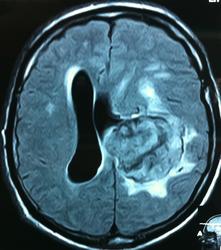

Начало вот здесь http://www.radiomed.ru/cases/kt-gms-obemnoe-obrazovanie-levoi-gemisfery-bolshogo-mozga-vnutrizheludochkovaya-meningioma. Пациент оперирован (меня сначала дезинформировали по поводу операции), перед операцией состояние ухудшилось, возникла правосторонняя гемиплегия, которая осталась и после декомпрессии. МРТ, КТ снимки и выписку предоставила супруга пациента, снимал на iphone, простите за качество, дисков с исследованиями не записывали. Надеюсь вопрос по данному случаю исчерпан.

FLAIR

КТ контроль после операции.

Мне видится так. Иначе в данной локализации просто неоткуда расти оболочечной опухоли. На контрольной КТ, после декомпрессии, когда срединные структуры стали действительно срединны, правое обызвествленное сосудистое сплетение видно отчетливо, а левое, где оно? Ведь если бы образование компремировало, то после операции, когда часть мозга пролабировало в трепанационное отверстие мы бы увидели и левое сосудистое сплетение, но оно интимно связано с образованием и даже "потянулось" за ним в сторону декомпрессионного отверстия, потому что это и есть "росток" откуда выросла опухоль.